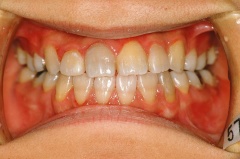

治療後 正面

正常になっています